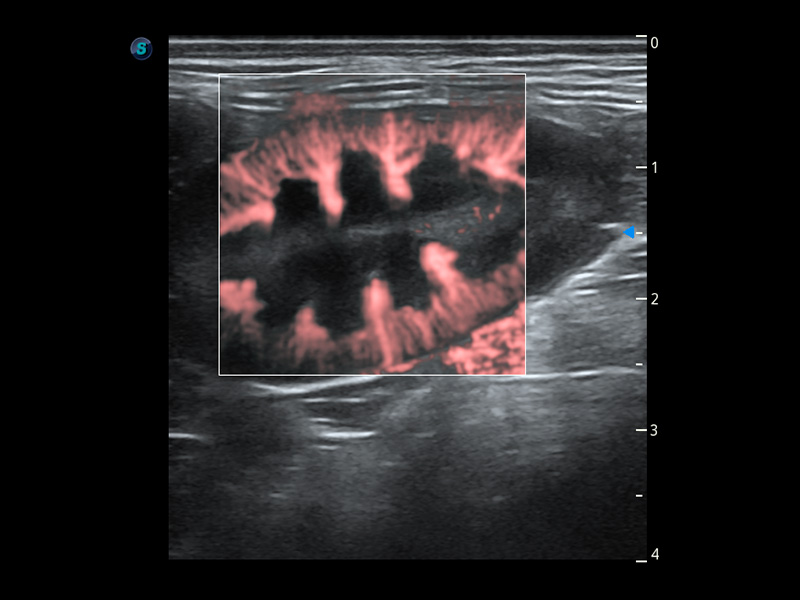

ProPet 60 作为一款高端台式动物超声设备,为动物医生的日常诊断提供了一系列贴合动物临床需求、解决临床实际问题的高级成像功能。凭借全系列高清探头,满足医生对腹部、心脏、生殖、浅表、肌骨等成像的所有需求,切实帮助您提升检查效率,提高诊断信心。

动物是人类最亲密的朋友和最值得信赖的伙伴。美狮贵宾会官网也一直致力于探索动物专用的超声影像解决方案。 全新推出的ProPet系列,是美狮贵宾会官网在动物超声影像智能化、专业化、精准化的一次跨越式革新。动物不能用言语来表述自己的不适,通过超声影像,ProPet系列搭建了动物医生与不同物种沟通的“桥梁”,为动物医生注入了“治愈之力”。